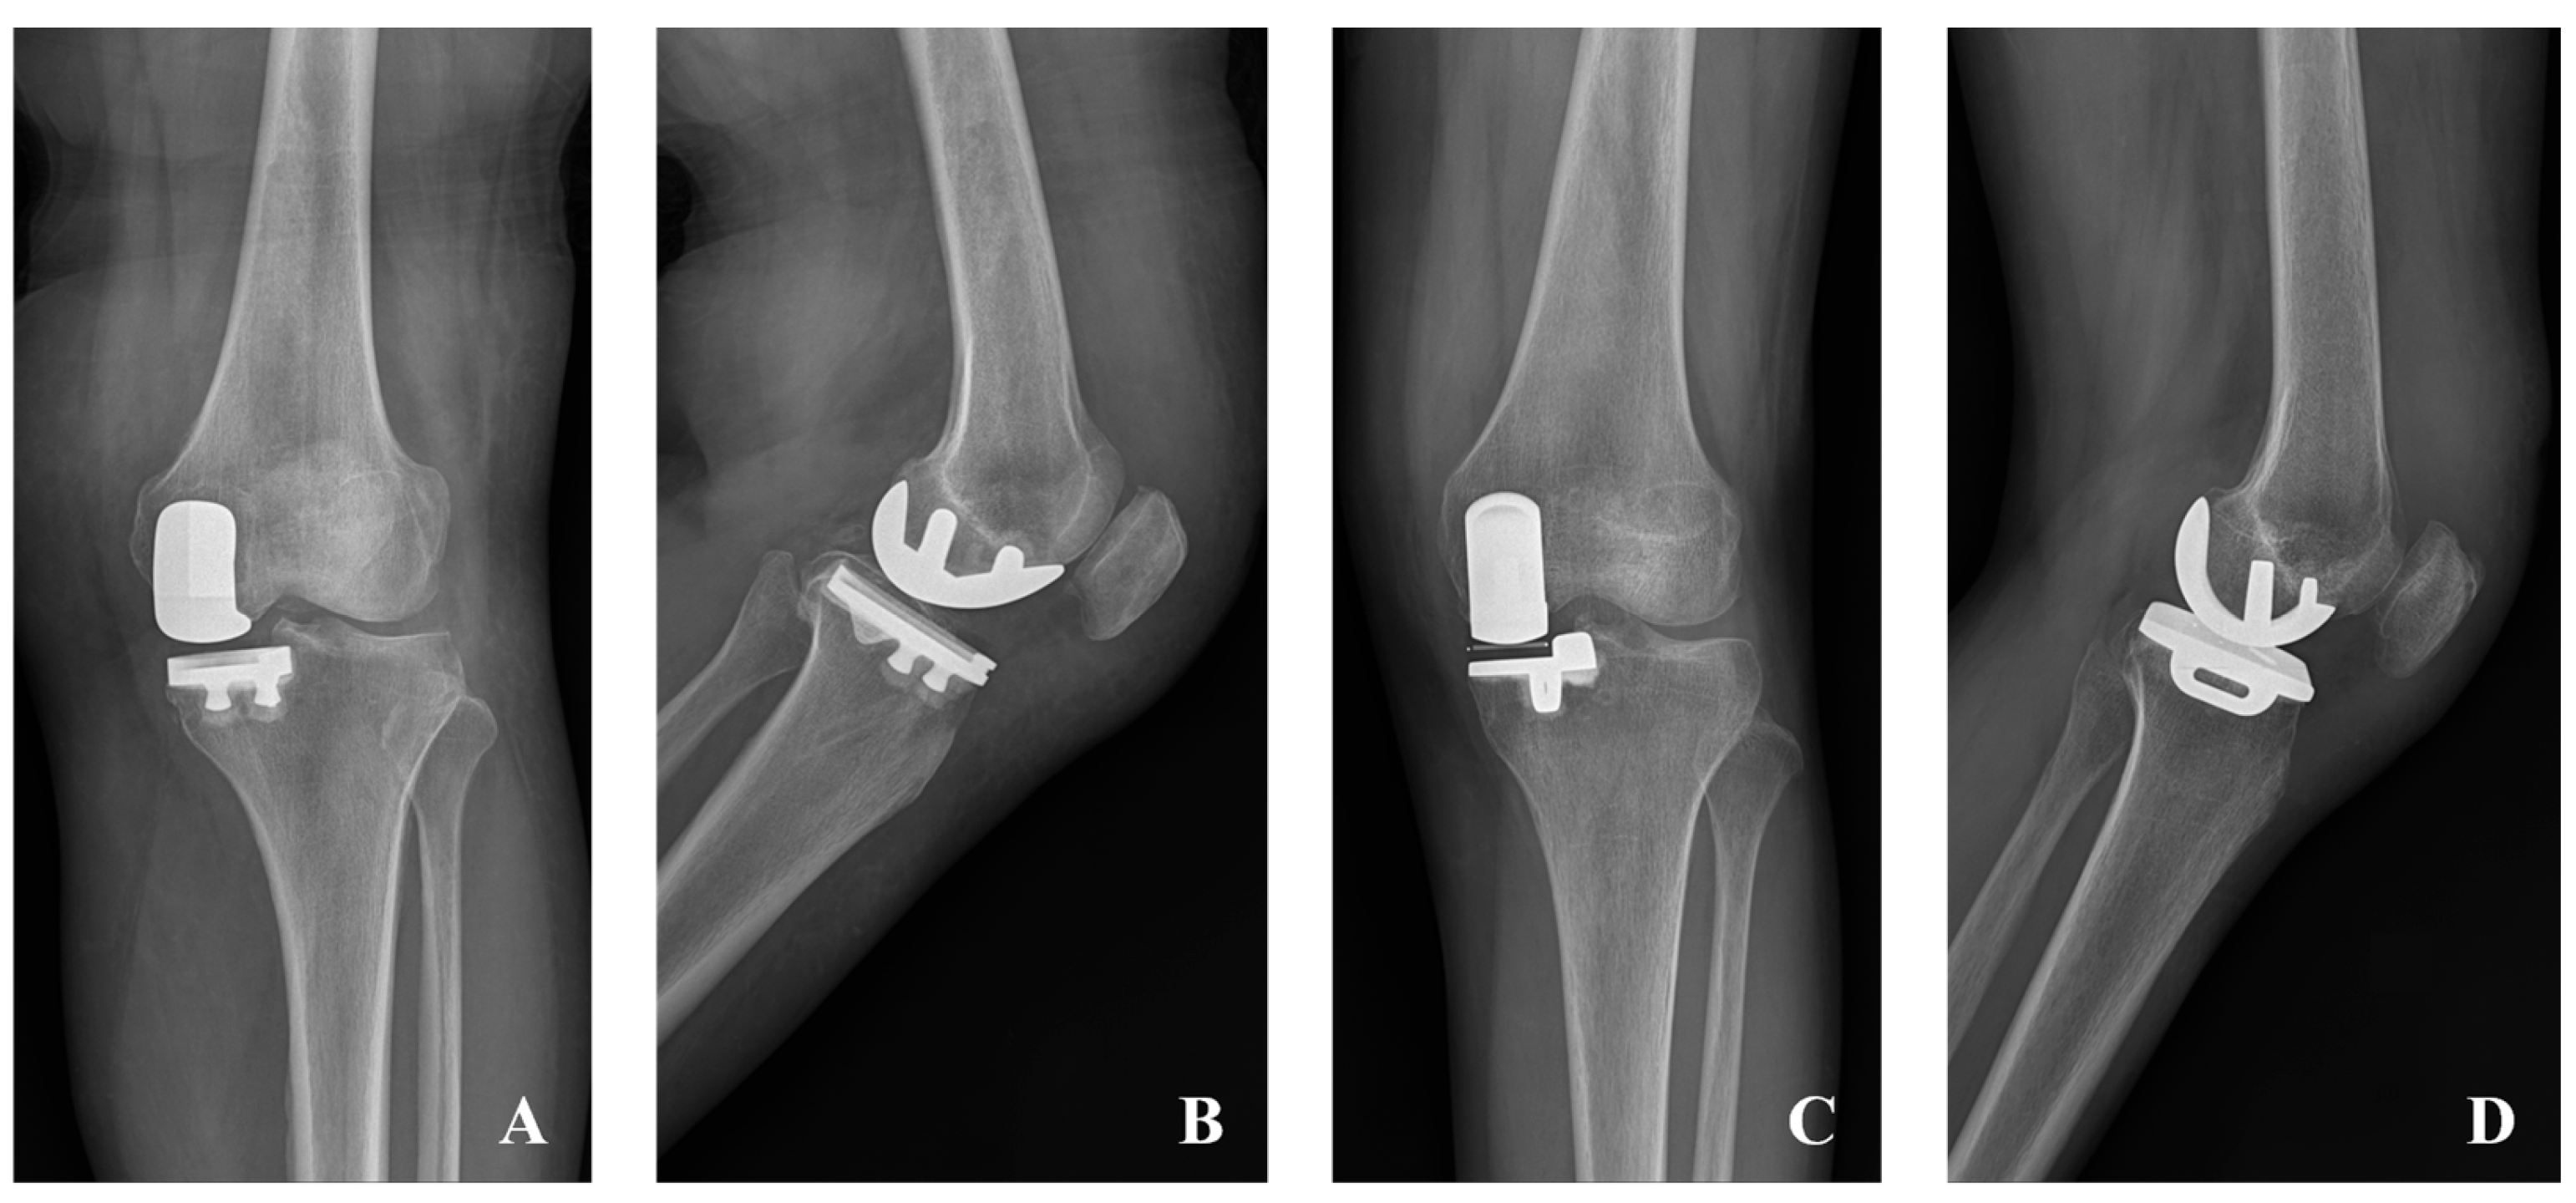

2.2. Surgical Treatment